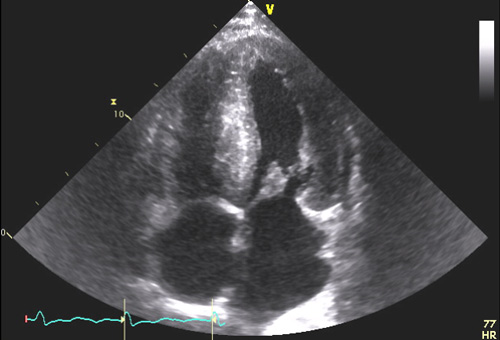

L’atteinte cardiaque secondaire à une amylose se présente généralement sous forme d’hypertrophie biventriculaire avec une hypertrophie ventriculaire gauche le plus souvent concentrique ou diffuse (Figure 1a), qui peut cependant parfois être modérée (12-13 mm). Généralement non obstructive, cette hypertrophie peut prédominer au niveau du septum interventriculaire et même prendre parfois l’aspect d’une cardiomyopathie hypertrophique sarcomérique. Il convient donc de la suspecter devant toute hypertrophie ventriculaire gauche (VG), surtout si celle-ci est concentrique ou diffuse, et si elle s’associe à d’autres éléments comme une hypertrophie de la paroi du ventricule droit (VD) (épaisseur de paroi >5 mm lors de la mesure réalisée en incidence sous-costale) (Figure 1b) avec dysfonction systolique assez fréquente sans être systématique.

Figure 1 : Aspects morphologiques échocardiographiques typiques d’amylose cardiaque

b- Hypertrophie VD mesurée à 9 mm en incidence sous-costale